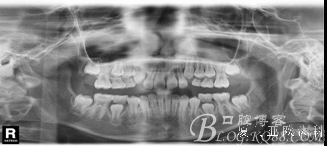

全頜曲面斷層片:尚未萌出的恒牙牙胚均存在。

診 斷:安氏I類錯(cuò)合(III類傾向)。骨骼III類關(guān)系。凹面型:上頜劣生長、下頜過生長。上頜尖牙萌出間隙不足。前牙骨性反咬合。